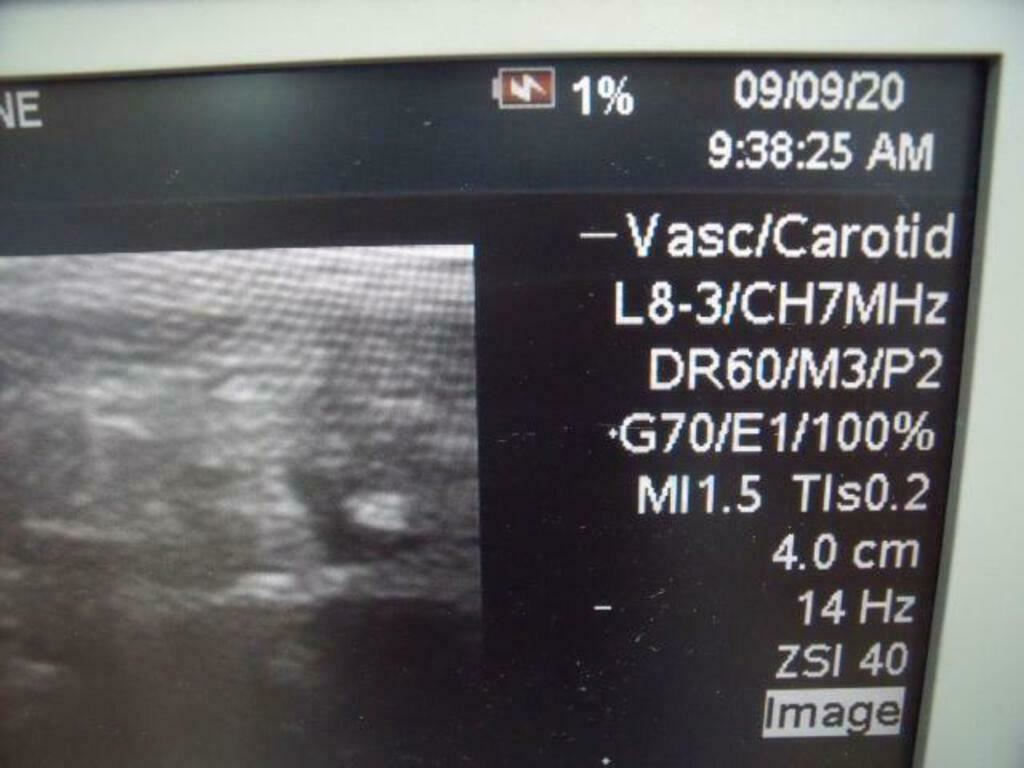

ZONARE 84007-30 L8-3 ULTRASOUND PROBE

In good condition, "as pictured."